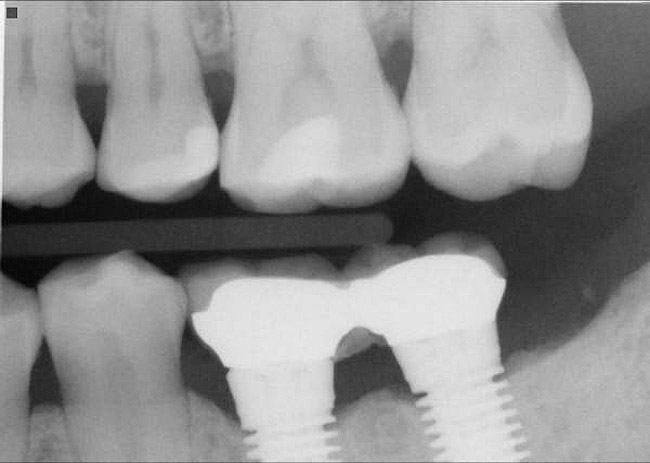

Horzontal Components of Implant Placement

The horizontal aspect of implant spacing is critical to avoid bone loss on adjacent teeth or implants. Single-tooth implants should be placed 1.5 mm to 2 mm from the adjacent teeth,19,20 and implants should have at least 3 mm of space between them21 (Figure 12). By keeping a minimum 1.5-mm distance from the adjacent tooth and a minimum distance of 3 mm between adjacent implants, angular defects resulting from crestal bone remodeling can be kept from becoming horizontal defects19-22 (Figure 13). This distance allows the bone on the adjacent tooth to stay at its current level. Conversely, if bone loss on the adjacent tooth or implant occurs, the bone loss will not affect the adjacent tooth or implant. This is especially critical in the anterior regions of the mouth where papilla height is more important for an esthetic result.23-27

Figure 12  Horizontal spacing needed between the natural tooth and the implants and between the adjacent implants.

Figure 12

Figure 13  Radiograph depicting the necessity of horizontal placement parameters to prevent vertical defects from becoming horizontal defects.

Figure 13